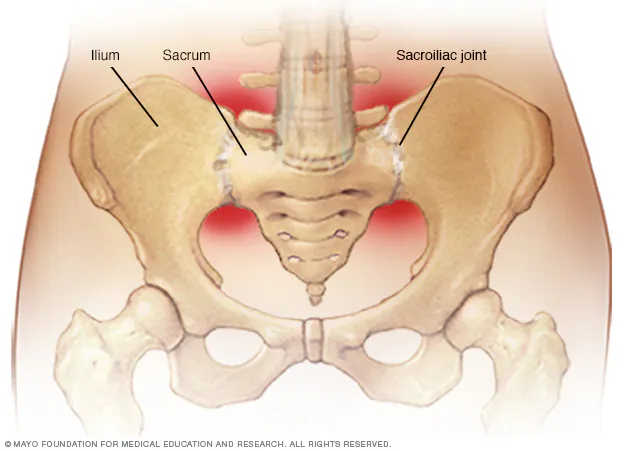

The sacroiliac (SI) joints are small but powerful joints located where your spine meets your pelvis. Each person has two SI joints, connecting the sacrum (the triangular bone at the base of the spine) to the iliac bones of the pelvis. These joints play an essential role in stabilizing the spine and transferring weight from the upper body into the lower extremities. Unlike the freely mobile joints in your arms and legs, the SI joints allow only limited motion—mostly a slight tilting and gliding—to provide both stability and shock absorption during walking, running, and lifting.

When the SI joint becomes irritated, inflamed, or unstable, the result is sacroiliac joint dysfunction. This condition is a common cause of low back pain, often mistaken for a lumbar disc problem or hip issue.

The hallmark symptom is pain in the lower back or buttock region, which may radiate into the hip, groin, or even the thigh. Many patients describe it as sharp, stabbing, or aching. The pain often worsens when standing up from a seated position, climbing stairs, or bearing more weight on one leg.